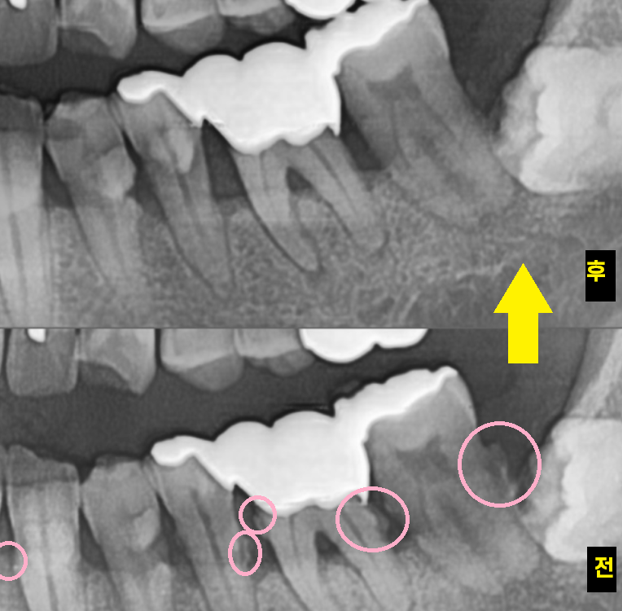

어쨌든 오늘 환자분 검사를 위해 촬영한 x ray

전반적으로 잇몸이 많이 내려가신 상황이었는데요.

221216

잇몸도 내려가고

치아가 전반적으로 닳고 깨진 부위도 관찰됩니다.

불편을 호소하신 오른쪽 치아

x-ray 상에서 잇몸뼈가 많이 내려가

x-ray상에서 치석이 관찰될정도면

왕 치석이라는 얘기입니다.

잇몸 관리 한지 오래 되셨다는 말이죠.

처음에는 조그맣게 뭉쳐있던 치석이

점점 몸 크기를 키워 x ray에 보일정도로...